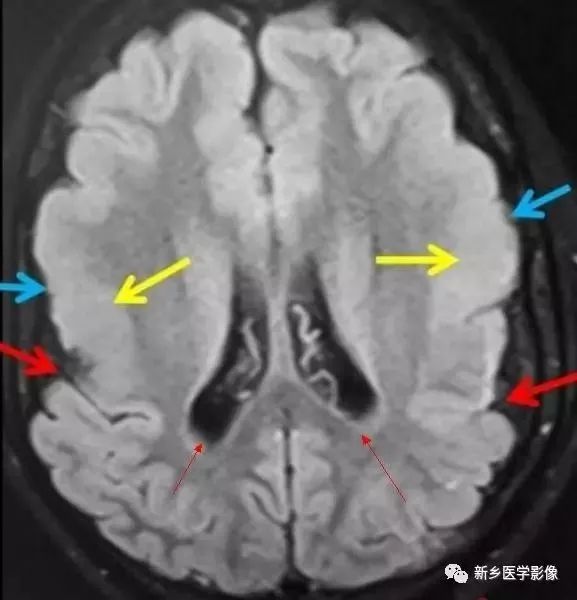

❶ 交通性脑积水

又称脑室外梗阻性脑积水,是由四脑室出口以后脑脊液循环通路障碍所致的脑积水。常位于蛛网膜下腔,以基底池最常见。

主要原因包括脑膜炎、蛛网膜下腔出血、脑膜转移、外伤、静脉窦血栓、颅脑手术后和脑脊液吸收功能障碍等。临床表现主要由颅压增高所引起.,可表现有头痛、呕吐、复视和视乳头水肿等。

交通性脑积水时,第四脑室扩大通常出现较晚,故早期时,可仅表现有侧脑室和三脑室扩大。主要应与导水管狭窄之梗阻性脑积水区别。MR矢状位T1加权图是直接观察导水管有无狭窄的最好方法。

另外需要与普遍性脑萎缩区别:脑萎缩时沟脑裂增宽,而脑积水时脑沟变窄消失或正常;脑萎缩时三脑室扩大较明显,脑积水时三脑室扩大不明显。到晚期,交通性脑积水出现整个脑室系统普遍扩大,而脑沟正常或变窄消失。